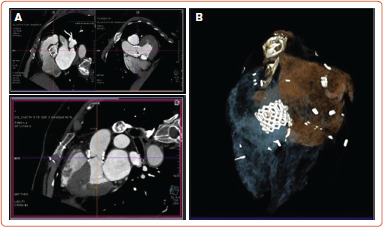

Results: A total of 116 patients were included. Hypo-attenuated leaflet thickening was detected in 11 patients. Only one had accompanying reduced leaflet mobility and an increase in gradient. This patient did not have any evidence of stroke or valve dysfunction. After switching to rivaroxaban, the gradient improved and a repeat cardiac CT demonstrated resolution of the leaflet thickening.